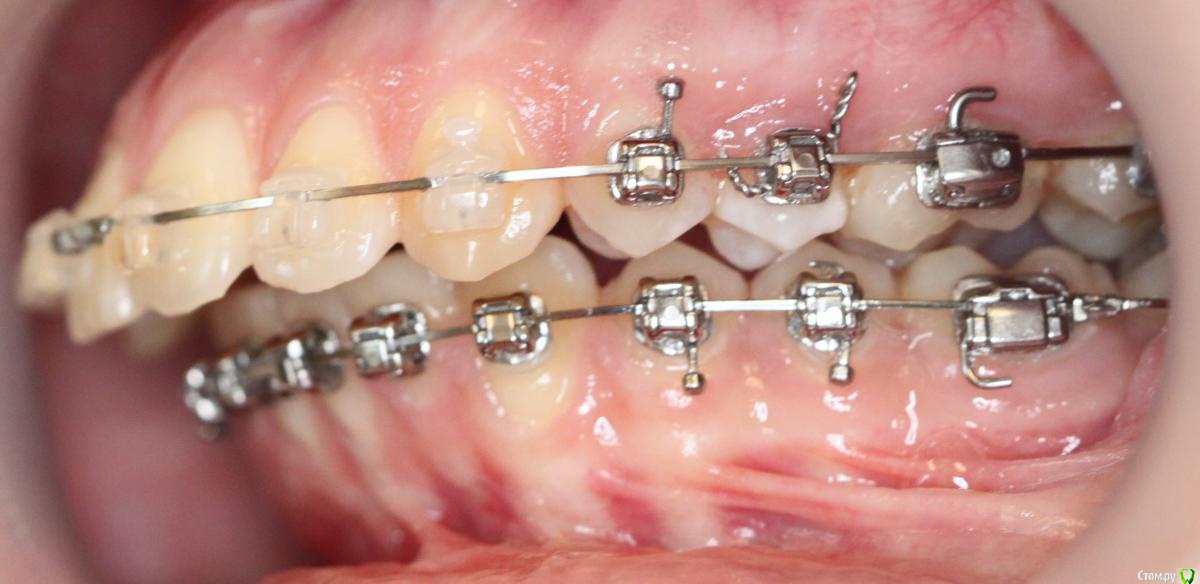

annurka Опубликовано 12 сентября, 2017 Поделиться Опубликовано 12 сентября, 2017 (изменено) здравствуйте! 24 года, дисфункция ВНЧС, дистальный прикус (1,4см), ортодонтическое лечение начато с ношения каппы для разгрузки сустава (привыкла подтягивать НЧ к верхней) в 2012 году. проведено лечение: удаление всех 8к (непрорезавшиеся), расширение ВЧ (аппарат дерихсвайлера), выравнивание зубных рядов, сепарация нижних резцов (резцы были наклонены), места не хватило - удаление 2 нижних 4к, выравнивание кривой шпее, двухчелюстная остеотомия; выравнивание окклюзионных контактов (резиновые тяги) проблема: между верхними и нижними резцами расстояние 5мм к трг (внизу фото) есть расшифровка.все идет к снятию брекетов, и с эстетической точки зрения меня все устраивает. но не до конца устраивает в функциональном плане (я не могу пропихнуть палец между зубными рядами, как раньше, но все также подтягиваю челюсть кпереди когда ем, говорю)стараюсь контролировать это, но даже улыбнуться не могу не подтянув - иначе у меня некрасиво вырисовывается подбородок, неправильно произношу звуки при разговоре.сразу после остеотомии состыковка резцов была ок - нижние зубы были за верхними, но мы с ортодонтом занялись состыковкой и других зубов (которые тогда не соприкасались), и когда добились контактов жующих сторон, разошлись резцы.UPD: и еще есть черные треугольники на НЧ - с ними тоже очень хочется разобраться лечащий ортодонт говорит, что это в целом норма, с учетом моего случая. и возможно это так, но я очень хочу послушать еще мнений, возможно стоит удалить 2 зуба наверху, чтобы верхняя челюсть подошла по размер нижней? [боюсь что простой сепарации может не хватить и как в случае с нижними резцами придется и сепарацию делать, и удалять зубы.] может быть еще есть другой способ добиться нормального прикуса, без "нюансов"?изначально я пошла на все это лечение, чтобы остановить разрушение сустава (однажды проснулась и не смогла рот даже открыть, еще до лечения), полагала, что брекеты и члх исправят если не ситуацию, то причину, но я все еще двигаю НЧ вперед к ВЧ. с остеотомии прошел почти год (поэтому на изменение картины эластиками я уже не надеюсь), брекеты ношу почти 4 года. заранее всем спасибо за отклик! Изменено 12 сентября, 2017 пользователем annurka 1 Ссылка на комментарий

annurka Опубликовано 13 сентября, 2017 Автор Поделиться Опубликовано 13 сентября, 2017 (изменено) А До лечения есть ТРГ посмотреть? И фото какие-нибудь?есть трг сверху - сразу после остеотомии, снизу - через полгода после (когда резцы отошли друг от друга на 5мм) до лечения вообще точно делал ортодонт (снимки, слепки, фото), если в клинике это сохранили, я смогу сфотографировать. далее фото в процессе лечения - 4ки нижние еще не удалены, один хирург был готов так оперировать, другой сказал, что наклон нижних резцов неправильный и нужно как и было запланировано удалить 4ки, сепарации недостаточно.челюсть расслаблена как есть: НЧ подвинута к ВЧ для наглядности: есть фото слепков того периода, но форум ругается на слишком большой размер. если нужно - уменьшу залью) Изменено 13 сентября, 2017 пользователем annurka 1 Ссылка на комментарий

annurka Опубликовано 14 сентября, 2017 Автор Поделиться Опубликовано 14 сентября, 2017 (изменено) Нет, я трг пока не могу рассчитать, чтобы это утверждать - на выходных только время будет, а пока с телефона смотрю. Предполагаю,да.Ну и плюс контакты зубы ищут правильные и смыкаются в разном положениивообще к обоим трг (до и нынешнее) я добавила расшифровку выше, или вы имеете ввиду те, что с титановыми конструкциями? мне все же хочется верить что это с зубами беда, и они новой челюсти не подходят, а не то что челюсть куда-то съехала.. в принципе, как и любому человеку, пережившему перемещение двух челюстей. еще есть такое фото, сделала его сразу после операции, швы не позволяли толком губы раскрыть, а рот нельзя было открывать на протяжении месяца, поэтому такое качество: http://i12.pixs.ru/thumbs/5/6/2/w1BZH71BWi_3410341_27523562.jpghttp://i12.pixs.ru/thumbs/5/5/3/4pJjOEAIq2_4300116_27523553.jpg там видно, что резцы сходятся как следует, а больше никаких контактов нет у других зубов. эластик (который скреплял от движения челюсть) в то же время создавал контакты клыков, носила только их месяца 4. фото через месяц после оп, тенденцию верхних резцов уже видно (но рот мне еще открывать нельзя было)http://i12.pixs.ru/thumbs/6/4/3/IMG5512JPG_8912889_27523643.jpghttp://i12.pixs.ru/thumbs/6/3/1/4pJjOEAIq2_7818185_27523631.jpghttp://i12.pixs.ru/thumbs/6/4/9/IMG5522JPG_8755357_27523649.jpghttp://i12.pixs.ru/thumbs/6/5/1/IMG5525JPG_1306296_27523651.jpg спустя 2 месяца после оп, стала жевать еду, открывать рот могла только на 2смhttp://i12.pixs.ru/thumbs/6/5/7/IMG9072JPG_6555113_27523657.jpghttp://i12.pixs.ru/thumbs/6/6/5/IMG9080JPG_2398494_27523665.jpghttp://i12.pixs.ru/thumbs/6/7/3/IMG9085JPG_1231417_27523673.jpg по ссылке доступно увеличенное изображение, спасибо Skip Изменено 14 сентября, 2017 пользователем annurka Ссылка на комментарий